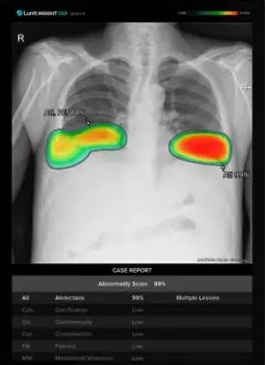

AI는 응급의료 시스템에서도 혁신을 이끌고 있다. 의료 AI 기업 딥노이드(315640)는 응급환자 진단의 정확도를 높이기 위해 딥뉴로(DEEP NEURO)와 딥체스트(DEEP CHEST) 솔루션을 개발했다.

딥체스트는 폐질환을, 딥뉴로는 뇌질환을 진단하는 AI 솔루션으로, 현재 마산의료원, 순천의료원 등 지역응급의료기관에서 활용되고 있다. 특히 딥체스트는 클라우드 기반으로 8개 보건소에 제공돼 의료 서비스가 부족한 지역에서도 신속한 진단과 치료를 가능하게 하고 있다.